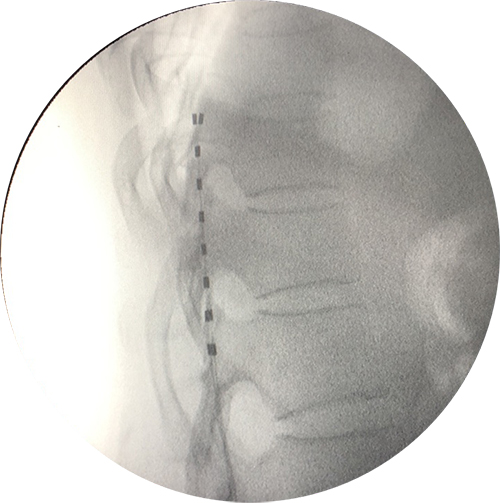

脊髓电刺激(spinal cord stimulation,SCS),俗称镇痛起搏器,是指将刺激电极置入椎管的硬膜外腔,通过电流刺激脊髓后角感觉神经元及后柱传导束,阻断疼痛信号传导,以达到治疗疼痛的一种神经调控方法。